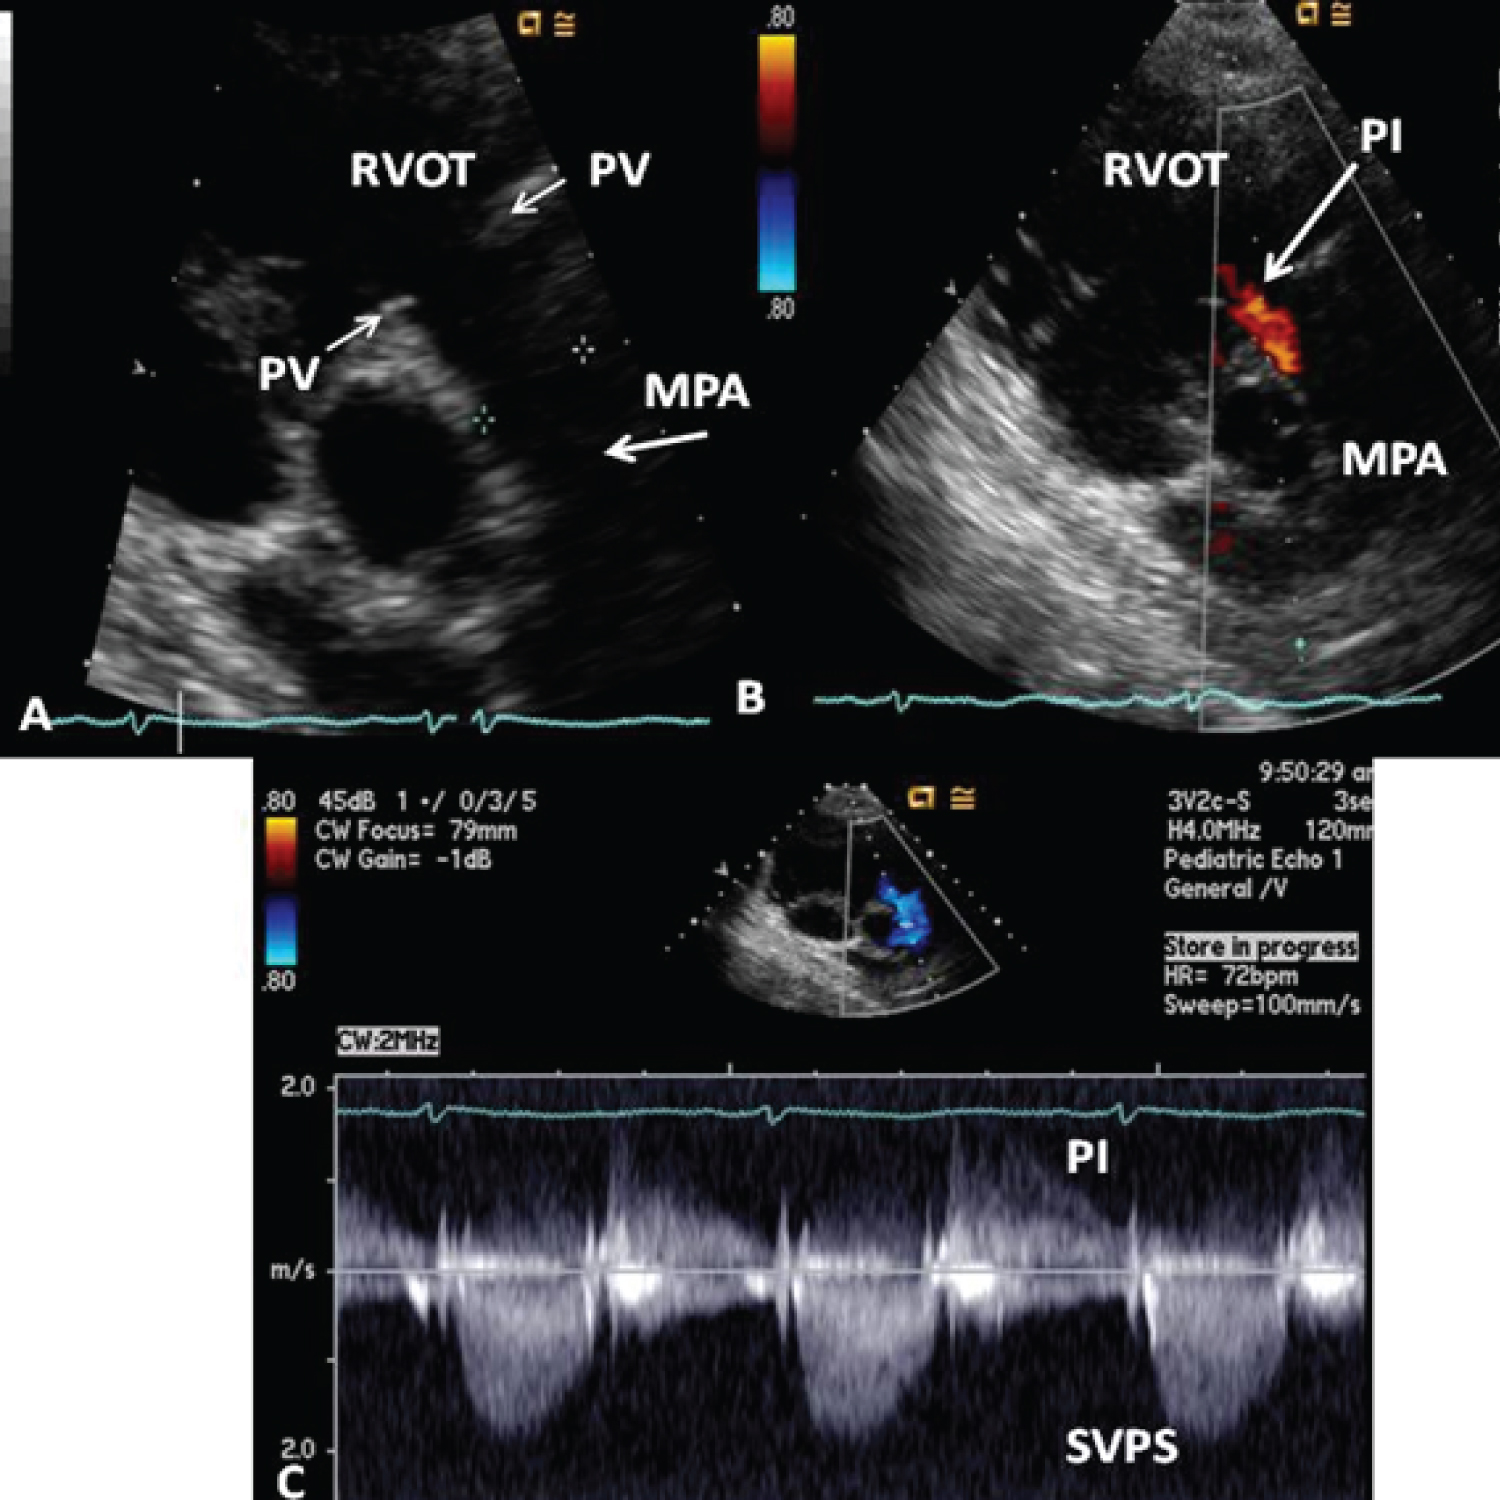

Figure 21: A) Selected video frame from a parasternal short axis view, showing echo-dense structures (thick blue arrows) within and outside the main pulmonary artery (MPA). The pulmonary valve (PV) leaflets (small arrows) are shown and appear normal. The right ventricular outflow tract (RVOT) and proximal MPA are free of any echo-dense structures; B) Color Doppler mapping of the same structures as in panel A shows normal laminar (L) flow in the RVOT and proximal MPA and turbulent (T) flow starting in the proximal MPA, indicating obstruction; C) Pulse Doppler sampling from the proximal MPA, which shows normal flow velocity; D) Continuous wave Doppler sampling demonstrating high velocity flow across the MPA, with a calculated peak instantaneous gradient of 93.7 mmHg and a mean gradient of 56 mmHg, indicating severe obstruction [154]. View Figure 21

Figure 22: Echo-Doppler studies performed five months after the removal of the Nuss bar. A) Selected video frame from a parasternal short axis view, demonstrating the absence of the echo-dense structures in the right ventricular outflow tract (RVOT) and main pulmonary artery (MPA) that were seen prior to the removal of the Nuss bar (Figure 22-32A). The pulmonary valve (PV) leaflets (arrows) are shown; B) Color Doppler mapping of the same structures as in panel A, showing mild pulmonary insufficiency (PI) (arrow); C) Continuous wave Doppler sampling, demonstrating a low Doppler flow velocity across the MPA with a calculated peak instantaneous gradient of 15 mmHg, indicating minimal supravalvular pulmonary stenosis (SVPS) and mild pulmonary insufficiency (PI) [154]. View Figure 22